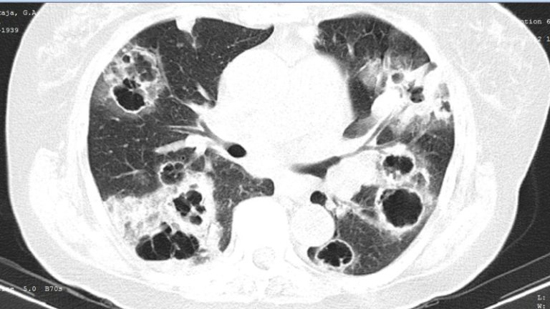

Рис. 10. КТ. Инвазивный острый аспергиллез легких. Множественные участки инфильтрации и полосные образования в легком.